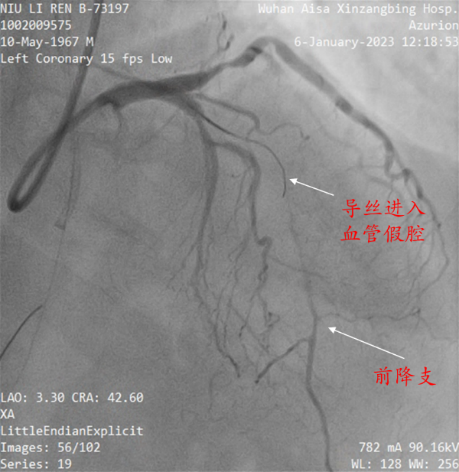

入院后立即完善术前检查和评估,第三天雷新军教授即带领景林德博士和李瑞峰住院医生为患者实施了手术,术中CAG显示:前降支7段和回旋支13段为CTO,因多次手术失败的原因,前降支7段存在明显的夹层和血肿病变,极大地增加了手术难度(图5)。经过缜密分析,雷新军教授决定首先尝试正向开通前降支CTO,若手术顺利再正向开通回旋支CTO,择期干预右冠脉。在不同体位造影指导下,雷新军教授仔细操控多种CTO导丝,历经约2小时终于成功开通了前降支和回旋支CTO,休息数天后又成功干预了右冠脉,手术效果良好(图6)。

图5 青海省人民医院造影资料